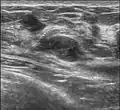

Fibroadenoma in ultrasound -